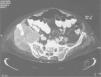

Masa glútea en anciana con enfermedad de Paget del hueso

A. Ballarín González, P. Laguna del Estal, H. de la Torre Martí, J.M. Palau Fayos

Servicio de Medicina Interna. Hospital Universitario Puerta de Hierro. Madrid. España